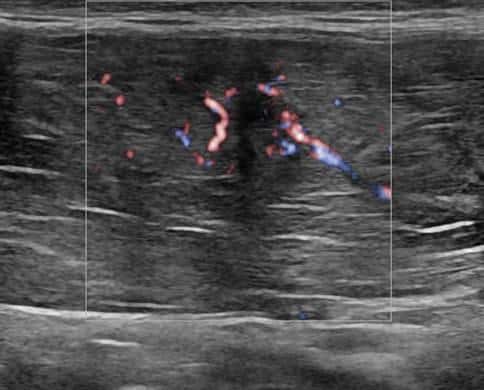

Chấn thương thành bụng

» Thông tin: Nam giới – 18 tuổi.

» Lâm sàng: Chấn thương thành bụng.

# Đụng dập, tụ máu cơ thành bụng.